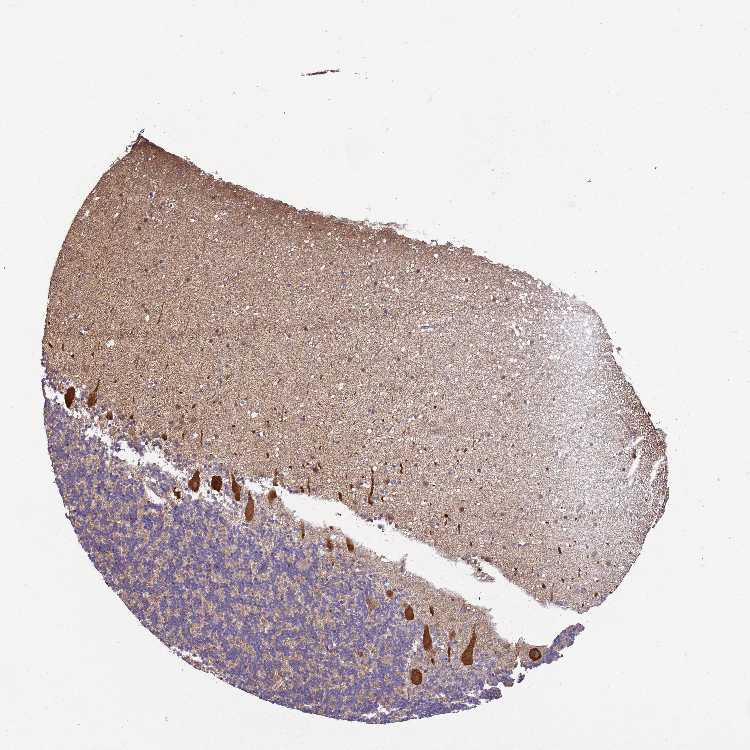

BRAIN CEREBELLUM Show tissue menu

CEREBELLUM - Expression summary

CEREBELLUM - Antibody stainingi

Antibody staining in the annotated cell types in the current human tissue is reported as not detected, low, medium, or high, based on conventional immunohistochemistry profiling in selected tissues. This score is based on the combination of the staining intensity and fraction of stained cells.

Each image is clickable and will lead to virtual microscopy that enables deeper exploration of all samples and also displays staining intensity scores, fraction scores and subcellular localization as well as patient and tissue information for each sample.

Antibody HPA028949Antibody CAB010143

Purkinje cells HighLow

Cells in granular layer LowNot detected

Cells in molecular layer LowNot detected